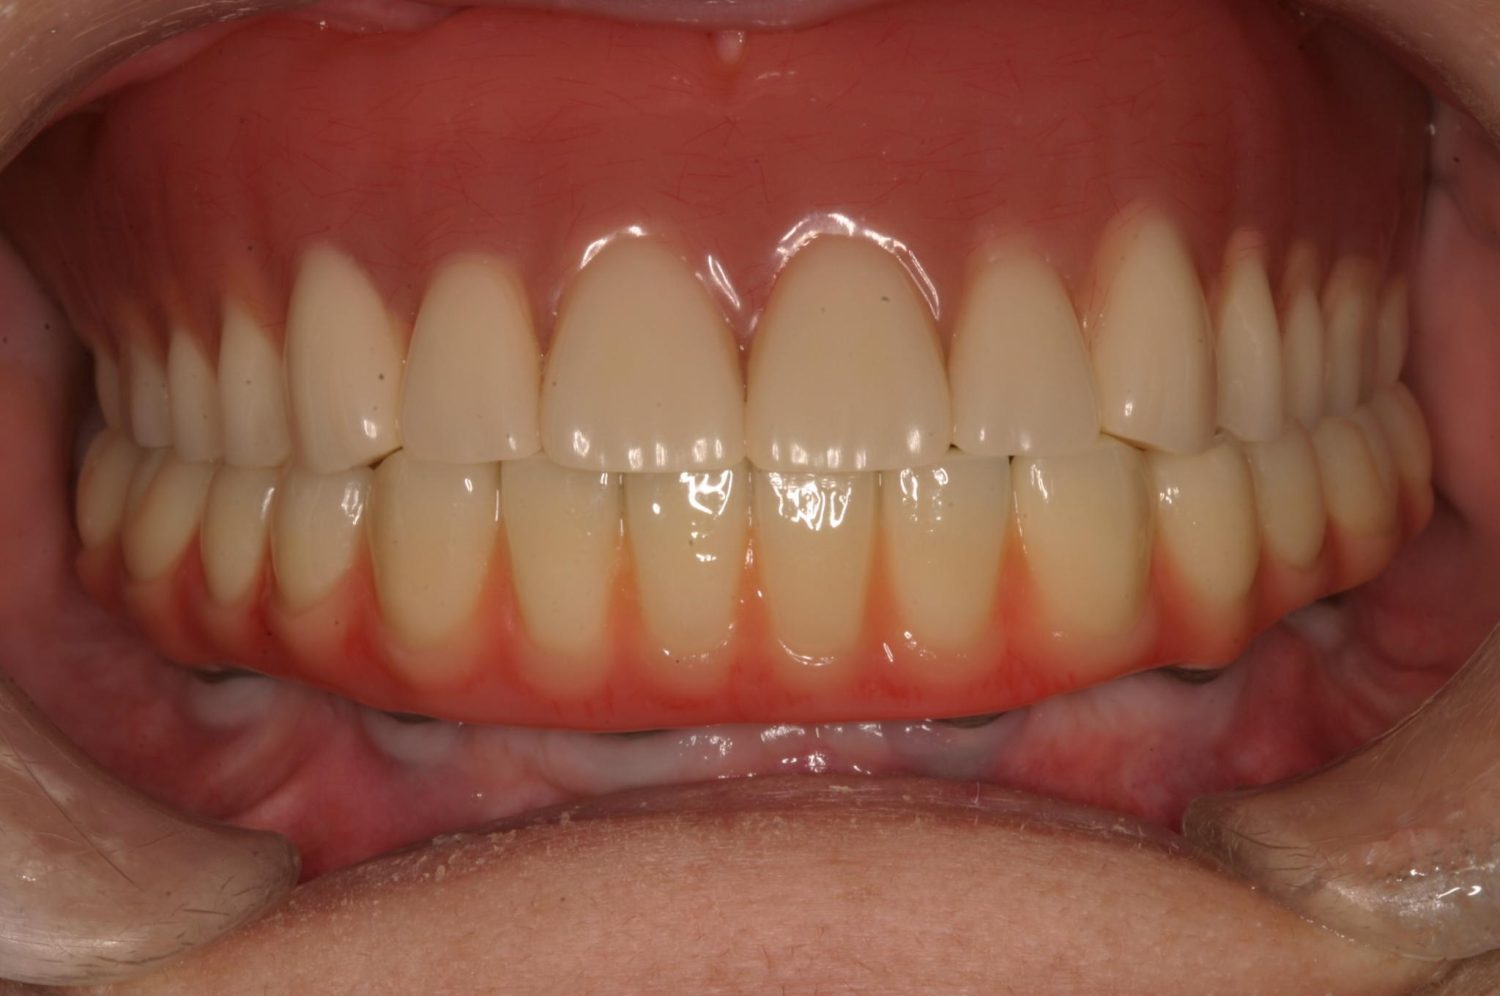

インプラント治療の症例紹介⑤

Before

After

主訴

歯肉腫脹、咬めるようにしたい

治療内容

重度歯周病により全ての残存歯保存不可能な状態。上下顎ボーンアンカードブリッジによる咬合再構成。

治療費

12,621,400円(税込)

治療期間

22ヶ月

通院回数

28回

想定されたリスク

※上部構造の形態が複雑になるため清掃が難しくなる、インプラント周囲炎の恐れがありました。

上顎8本下顎7本のインプラント体埋入によるボーンアンカードブリッジ。